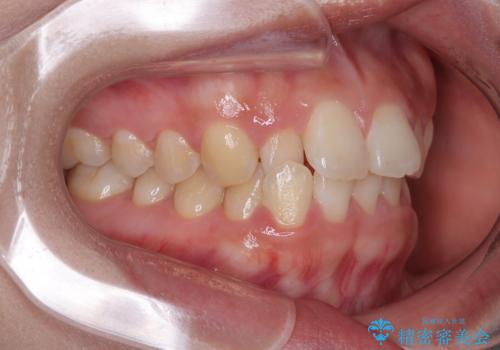

- 前歯のデコボコが気になるでのことで来院された患者様です。

歯列アーチが狭くスペース不足により前歯がデコボコしている状態でした。見た目を改善しつつ、前歯を前方に突出させず、自然な笑顔を目指したいというご希望でした。

・アーチを側方に拡大して歯が並ぶスペースを確保

・抜歯は避け、非抜歯での対応